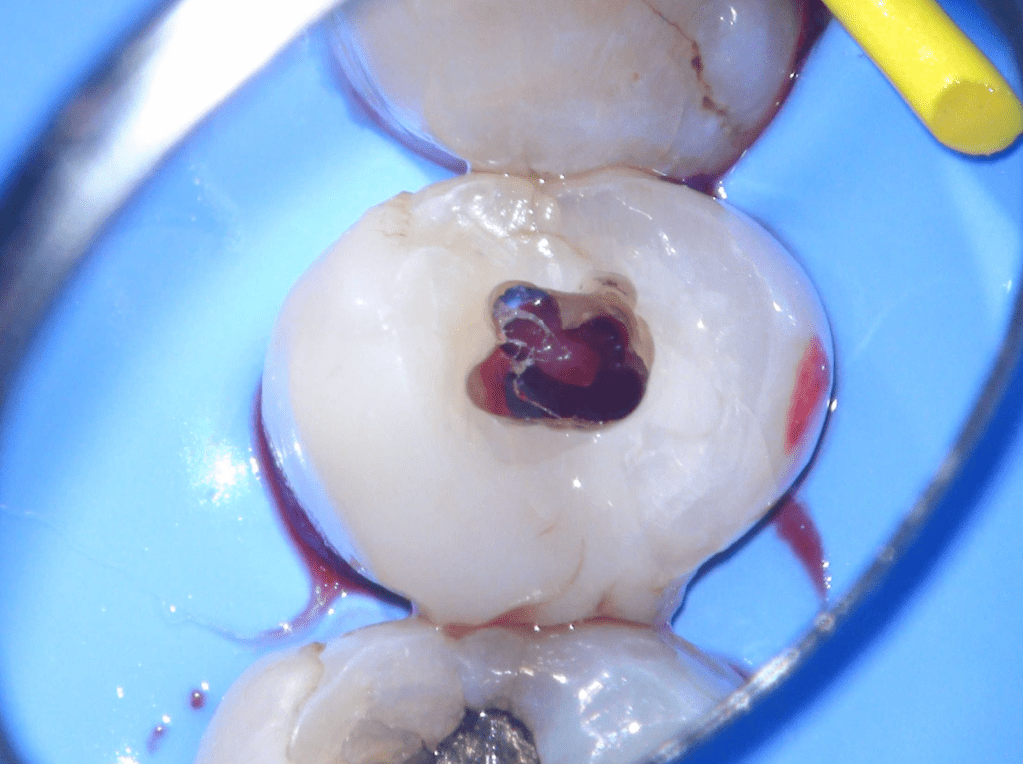

Gingivectomía + pulpotomía biodentine + reconstrucción

Pulpotomía biodentine + reco preendio

Pulpotomías